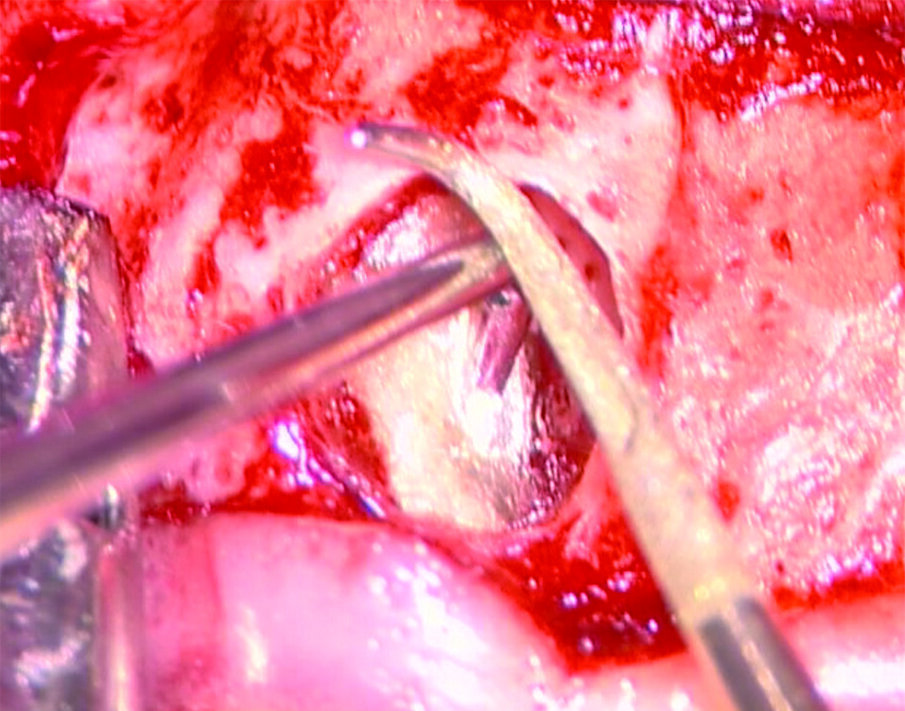

Tali perforazioni sono piuttosto frequenti a livello degli incisivi superiori, dove l’errore che più spesso viene commesso è rappresentato dall’utilizzo della fresa con eccessiva angolazione vestibolare. Perforazioni del terzo coronale possono anche accadere sul pavimento dei molari quando gli orifizi canalari vengono cercati in posti sbagliati. Tipiche sono le perforazioni nei molari superiori o inferiori, che avvengono per lo sfondamento del pavimento della camera pulpare (Figg. 3a-3i). Come conseguenza del trauma meccanico, si ha una rapida distruzione del legamento parodontale. L’osso alveolare immediatamente adiacente alla perforazione si riassorbe con conseguente perdita verticale di osso. Il processo infiammatorio quindi si estende coronalmente lungo le fibre del legamento parodontale, con distruzione del legamento, dell’osso alveolare e delle fibre gengivali sopracrestali. Come conseguenza di ciò, si ha la migrazione apicale dell’attacco epiteliale e le formazione di un grave difetto parodontale9.

Riparazione delle perforazioni mediante l’uso di MTA

La prognosi delle perforazioni è enormemente migliorata dopo l’introduzione dell’utilizzo del microscopio operatorio14 e del materiale biocompatibile MTA15, messo a punto da Torabinejad e coll.16 circa a metà degli anni ’90. Si tratta di un cemento endodontico estremamente biocompatibile, idrofilo e capace di stimolare processi di guarigione e osteogenesi17, 18. È una polvere di fini triossidi e altre particelle idrofile che induriscono in presenza di umidità. L’idratazione della polvere, infatti, dà luogo ad un gel colloidale che solidifica in una struttura dura in circa 3/4 ore. Tale cemento è diverso da tutti gli altri materiali usati per la sua biocompatibilità, per la sua attività antibatterica, per il suo adattamento marginale, per le sue capacità sigillanti ma soprattutto perché è idrofilo e quindi è resistente all’umidità.

La sequenza operativa per sigillare una perforazione della radice o del pavimento di una camera pulpare è la seguente:

- Detergere la sede della perforazione con le comuni irrigazioni a base di ipoclorito di sodio e, se i margini della perforazione sono raggiungibili, con le punte da ultrasuoni;